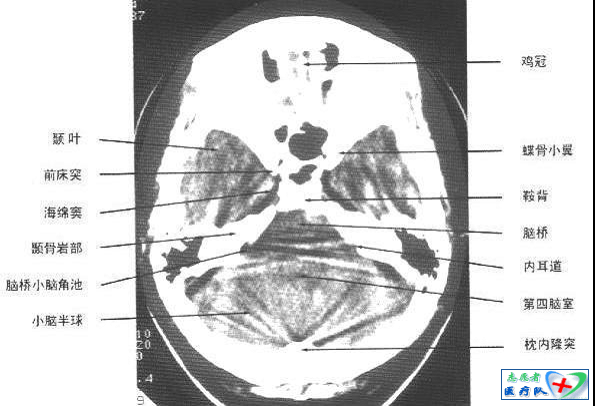

照片描述:颅底蝶鞍层面